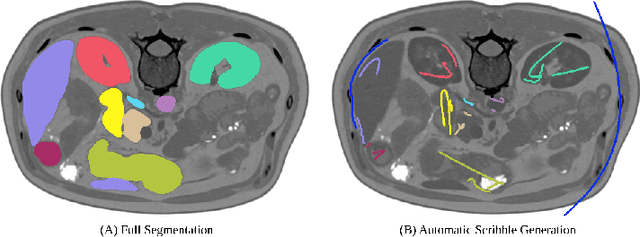

Abstract:Traditionally, segmentation algorithms require dense annotations for training, demanding significant annotation efforts, particularly within the 3D medical imaging field. Scribble-supervised learning emerges as a possible solution to this challenge, promising a reduction in annotation efforts when creating large-scale datasets. Recently, a plethora of methods for optimized learning from scribbles have been proposed, but have so far failed to position scribble annotation as a beneficial alternative. We relate this shortcoming to two major issues: 1) the complex nature of many methods which deeply ties them to the underlying segmentation model, thus preventing a migration to more powerful state-of-the-art models as the field progresses and 2) the lack of a systematic evaluation to validate consistent performance across the broader medical domain, resulting in a lack of trust when applying these methods to new segmentation problems. To address these issues, we propose a comprehensive scribble supervision benchmark consisting of seven datasets covering a diverse set of anatomies and pathologies imaged with varying modalities. We furthermore propose the systematic use of partial losses, i.e. losses that are only computed on annotated voxels. Contrary to most existing methods, these losses can be seamlessly integrated into state-of-the-art segmentation methods, enabling them to learn from scribble annotations while preserving their original loss formulations. Our evaluation using nnU-Net reveals that while most existing methods suffer from a lack of generalization, the proposed approach consistently delivers state-of-the-art performance. Thanks to its simplicity, our approach presents an embarrassingly simple yet effective solution to the challenges of scribble supervision. Source code as well as our extensive scribble benchmarking suite will be made publicly available upon publication.